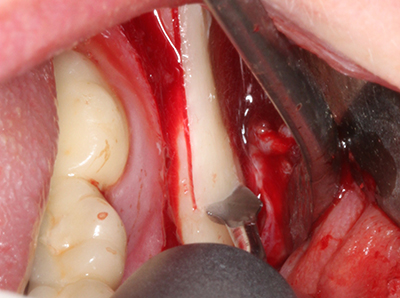

Sollen chirurgische Eingriffe mit unmittelbarer Knochenbeziehung an empfindlichen Strukturen wie Blutgefäßen oder Nerven erfolgen, so bergen rotierende Instrumente ein erhebliches Potential an iatrogener Schädigung. Gerade bei Nervdarstellungen nach iatrogener Schädigung, oder aber im Zuge einer Nervlateralisation für resektive und rekonstruktive Eingriffe oder Implantatinsertionen können piezoelektronische Geräte hilfreich sein Knochendeckel zu präparieren und nervnahe Hartgewebsanteile zu entfernen (Abb. 17-20). Ein leichter Kontakt des Nervstrangs zur Piezospitze bleibt dabei in der Regel folgenlos – allerdings kann eine unvorsichtige Vorgehensweise mit sägeartigen Bewegungen bzw. Ansätzen bei noch vorhandener knöcherner Unterlage durchaus temporäre oder aber auch permanente Nervschädigungen verursachen. Das Risiko einer solchen Schädigung wird jedoch als wesentliche geringer eingeschätzt als unter Anwendung von Säge- oder Fräsinstrumenten (Pereira, Gealh et al. 2014).

Abb. 17a: CT-Aufnahme eines wachstumsprogredienten Osteoms in unmittelbarer ...

Abb. 17b: Lagebeziehung zum Alveolarkanal mit Nervirritation (laterale und koronare Ansicht).

Abb. 18: Präparation eines Kortikalis-Deckels mit der Piezo-Knochensäge (Piezomed, W&H).

Abb. 19: Operationssitus nach Neurolyse und Osteomentfernung.

Abb. 20: Der entnommene Knochendeckel wird readaptiert und durch eine Osteosyntheseschraube (KLS Martin, Tuttlingen) fixiert.